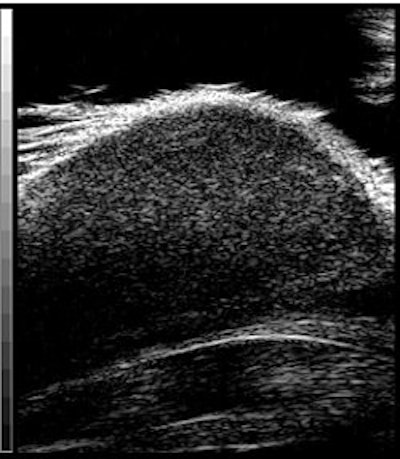

![]() |

Above, ultrasound image of NHL xenograft done on a 20-MHz transducer at 24 hours after CHOP chemotherapy. The apoptotic areas correspond to the areas of high-intensity backscatter. Below, corresponding histology image with TUNEL stain. The areas that are stained brown correspond to the apoptotic areas. Images courtesy of Dr. Charles Cho.